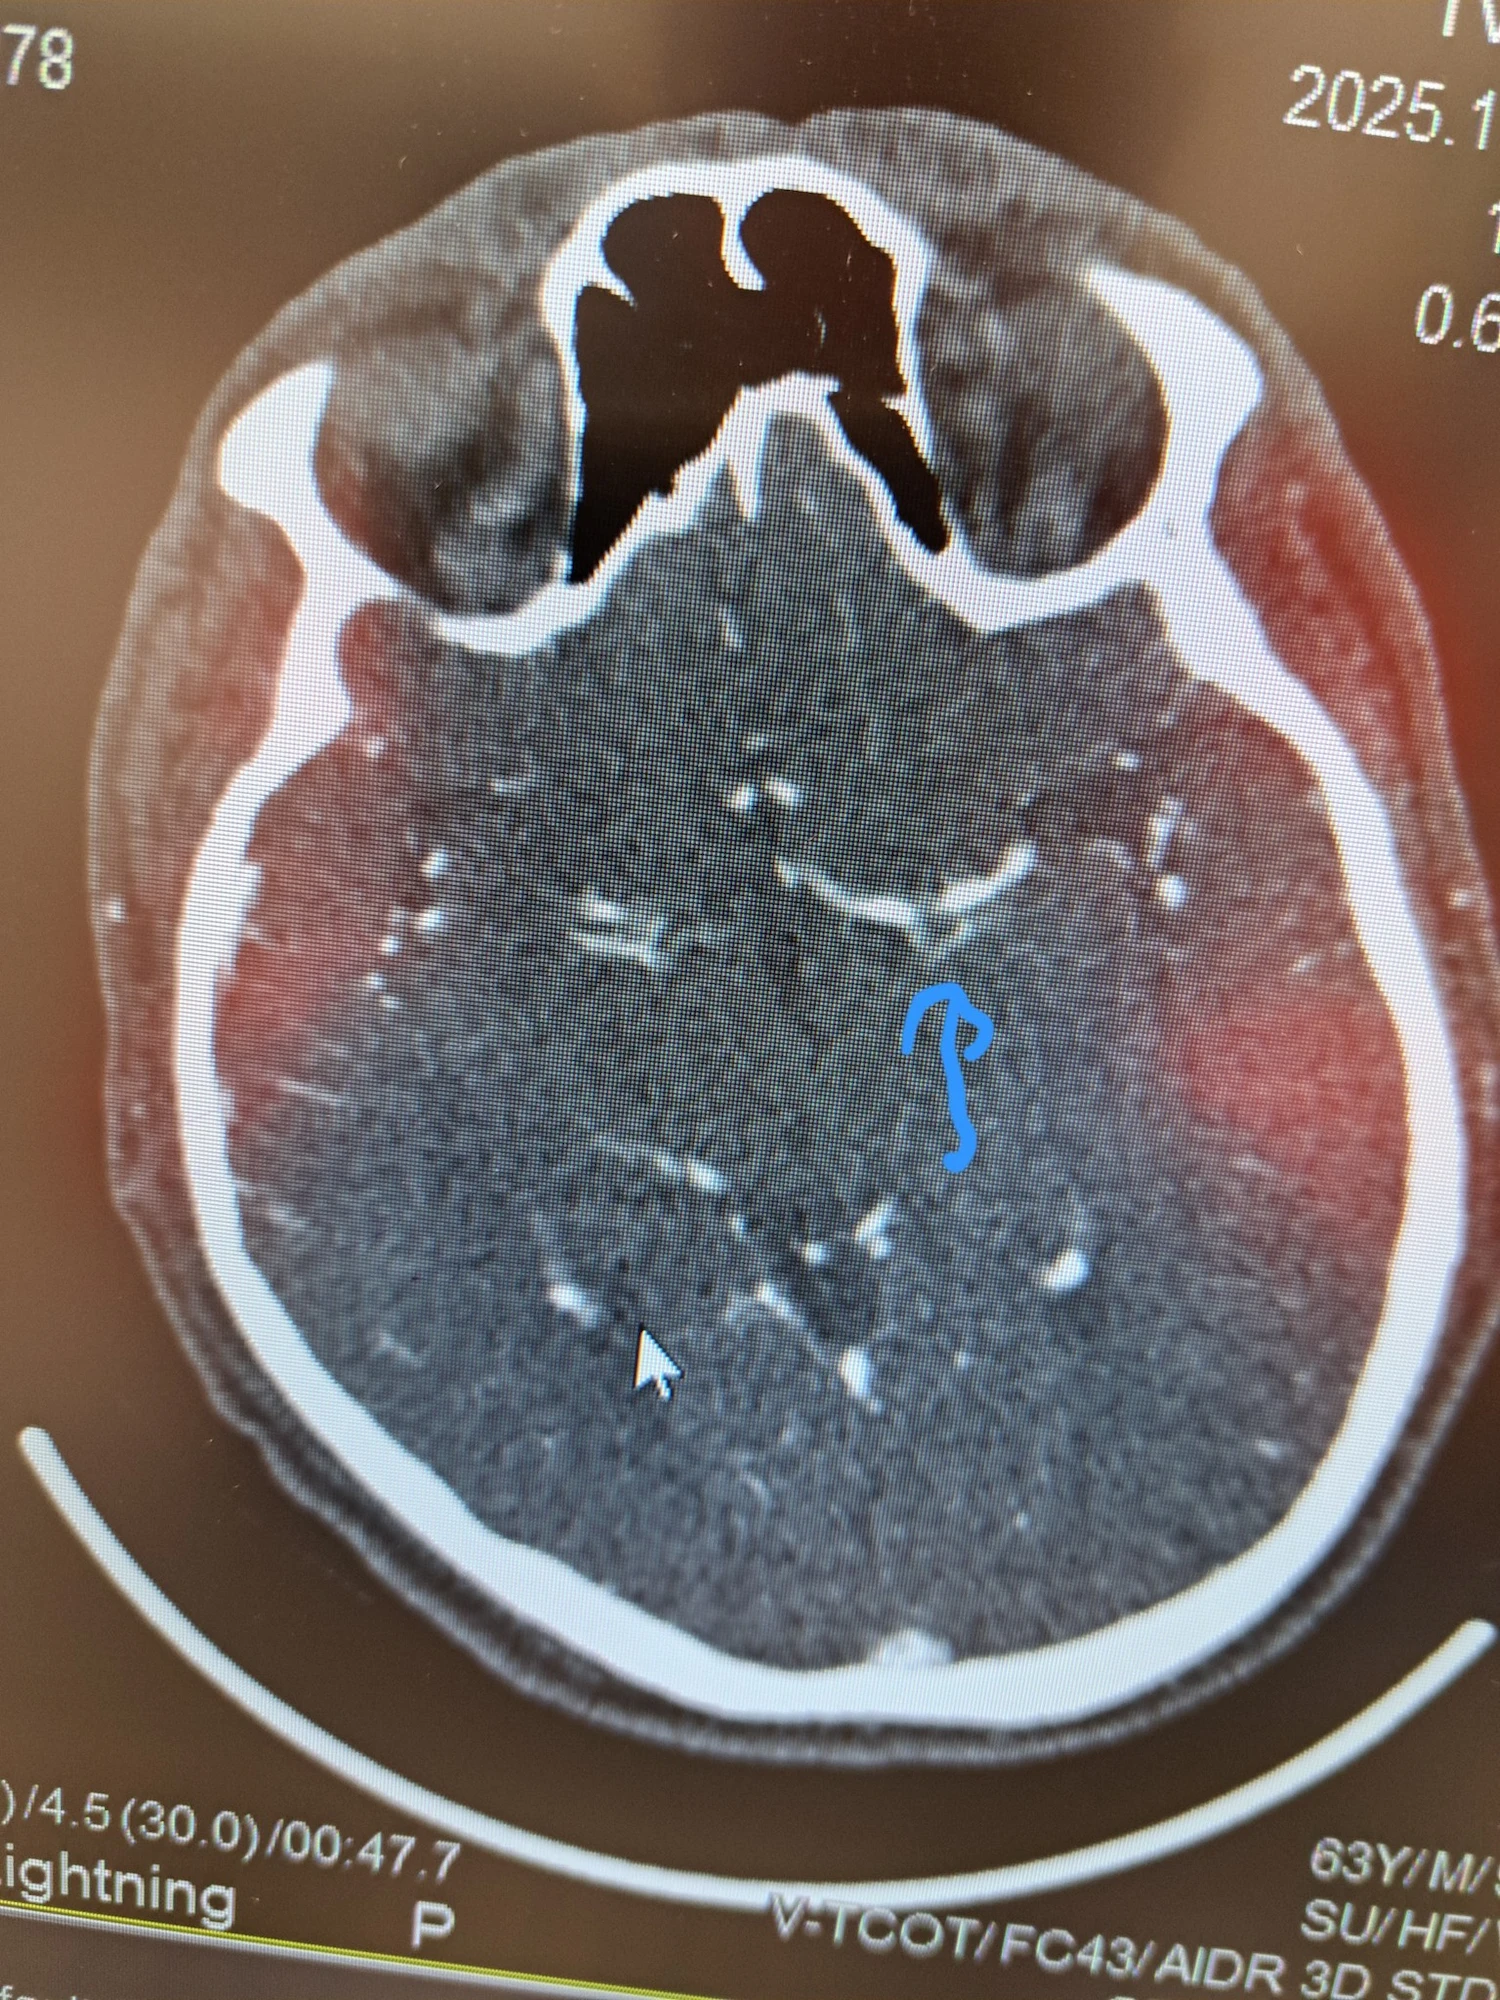

Len o päť minút neskôr, o 13:21, CT mozgu ukázalo dobrú správu, nešlo o krvácanie, čo znamená, že pacient môže dostať liečbu na rozpustenie zrazeniny.

Ešte pred samotným liečením lekár pomocou ultrazvuku srdca videl, že sa v ňom pravdepodobne nachádza zrazenina. To potvrdzovalo podozrenie, že k mŕtvici došlo práve kvôli nej. Potom prišlo detailné vyšetrenie ciev v mozgu. O 13:25 bolo jasné: upchatá je tepna na ľavej strane mozgu. Ak by sa zrazenina neodstránili okamžite, pacient by mohol prísť o reč aj schopnosť hýbať pravou polovicou tela.